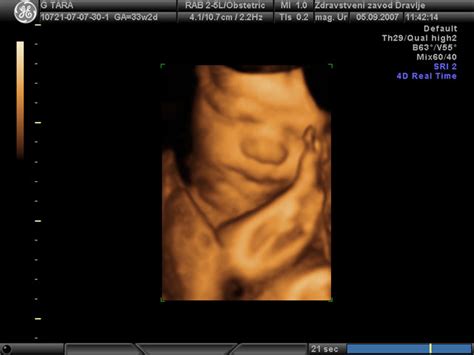

Insuficientno maternično ustje, kar pomeni, da maternično ustje ni dovolj močno, da bi zadržalo nosečnost do konca, je pomemben dejavnik tveganja. Ženske s kratkim materničnim vratom, ki ga je mogoče izmeriti z vaginalnim ultrazvokom, imajo večjo verjetnost za prezgodnji porod. Klasično se dolžina materničnega vratu meri med 20. in 24. tednom nosečnosti. Pri prvorodnicah lahko krajši maternični vrat od 15 mm nakazuje na veliko verjetnost prezgodnjega poroda, pri dvojčkih pa je ta kritična dolžina okvirno 25 mm.

- Redni pregledi in ultrazvočna meritev materničnega vratu: Ključni za zgodnje odkrivanje tveganja. Povišan cervikalni fibronektin lahko nakazuje na prezgodnji porod.